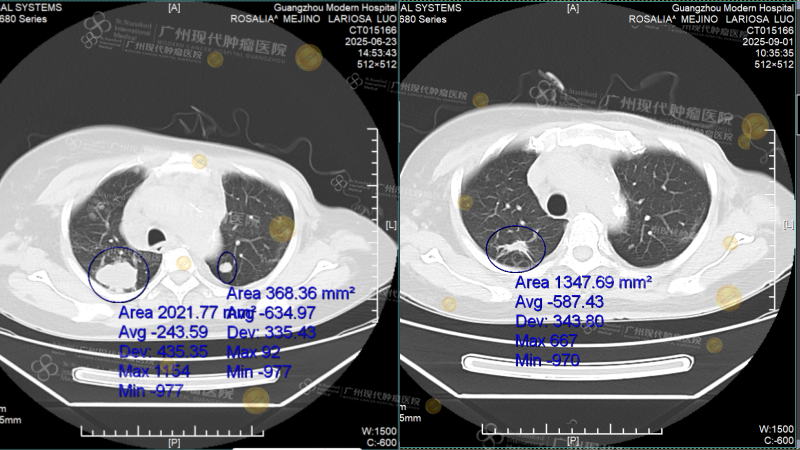

Sau đợt điều trị đầu tiên, kết quả tái khám cho thấy tổng thể khối u trong cơ thể bà đã thu nhỏ hơn 50%. Còn kết quả sau đợt điều trị thứ hai thì chính bà gọi đó là “phép màu”: phim CT cho thấy toàn bộ khối u ở cột sống thắt lưng đã biến mất; một bên phổi trở nên sạch gần như hoàn toàn; nốt ở cổ vốn từng to dần lên cũng đã được “làm tan biến”. Báo cáo kiểm tra mới nhất càng mang đến tín hiệu gần như thắng lợi toàn diện: hai lá phổi về cơ bản đã trở nên rõ sạch, phần bóng mờ nhỏ còn lại cũng đang tiếp tục giảm đi, chức năng tim và các chỉ số viêm đều đã trở về bình thường.

Hình ảnh CT đối chiếu trước và sau điều trị

(Trái: trước điều trị, 23/06/2025; Phải: sau điều trị, 01/09/2025)